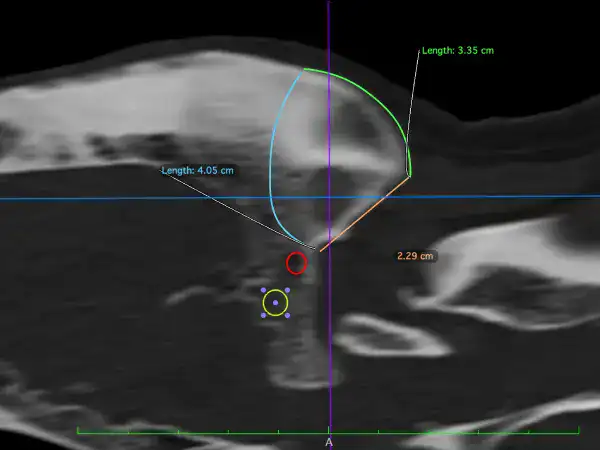

Beau, a 7-year-old male neutered German Shepherd, was referred to us in June 2025 for investigation and treatment of a slow-growing mass on the back of his skull.

CT confirmed an osteoproliferative mass originating from the nuchal crest, the appearance of which was typical for multilobular tumour of bone, also known as a multilobular osteochondrosarcoma (MLO). The histopathological diagnosis of MLO was confirmed with a minimally invasive biopsy.